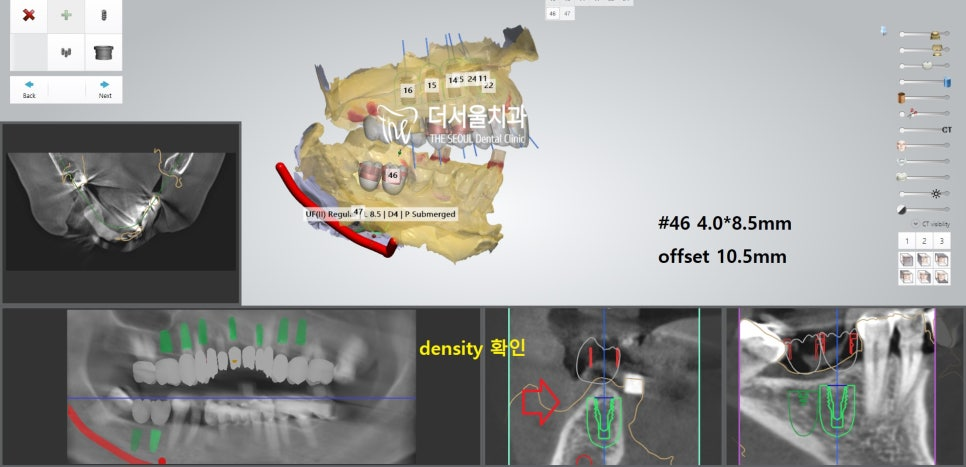

더서울에서 항상 했던 그대로

디지털 분석을 통해 인접치,

주변 조직과의 위치 관계를 파악했습니다.

계산된 위치에 맞춰 픽스쳐를 심어드렸습니다.

개수가 많기 때문에 걱정이 되었지만,

미리 제작된 가이드를 사용하여 수술을 진행하였더니

즉시식립 임플란트 과정을

정확하고 안전하게 끝마칠 수 있었습니다.